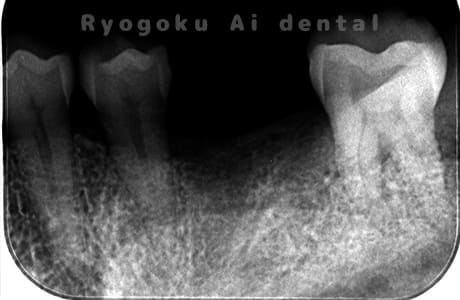

Case08

-

- 原因

- 左下7番歯根破折

- 治療内容

- インプラント治療

- 治療費用

- 約600,000円

左下の腫れが治らないとの事でご来院された患者様です。歯が割れていたため、抜歯を行い、骨に代わるお薬を入れ、インプラントを埋入致しました。経過良好で大変満足していただけました。

<リスク・副作用>

治療後、痛みや違和感、出血、腫れなどが出る事があります。喫煙者、糖尿病などの方の場合、歯が生着しない場合があります。